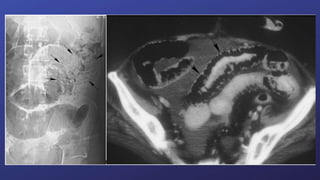

Avaliação e Diagnóstico:

O padrão atual -TC abdominal com contraste.

• Visualização do ponto de transição, gravidade da obstrução, potencial etiologia e avaliação de

complicações com risco de vida.

• Radiografia de abdome.

• Avaliação laboratorial - leucocitose, distúrbios eletrolíticos - êmese.

• TC é útil quando Rx não esclareceu a origem da obstrução. Auxilia na identificação de massas,

estadeamento das lesões e determina o nível da obstrução.